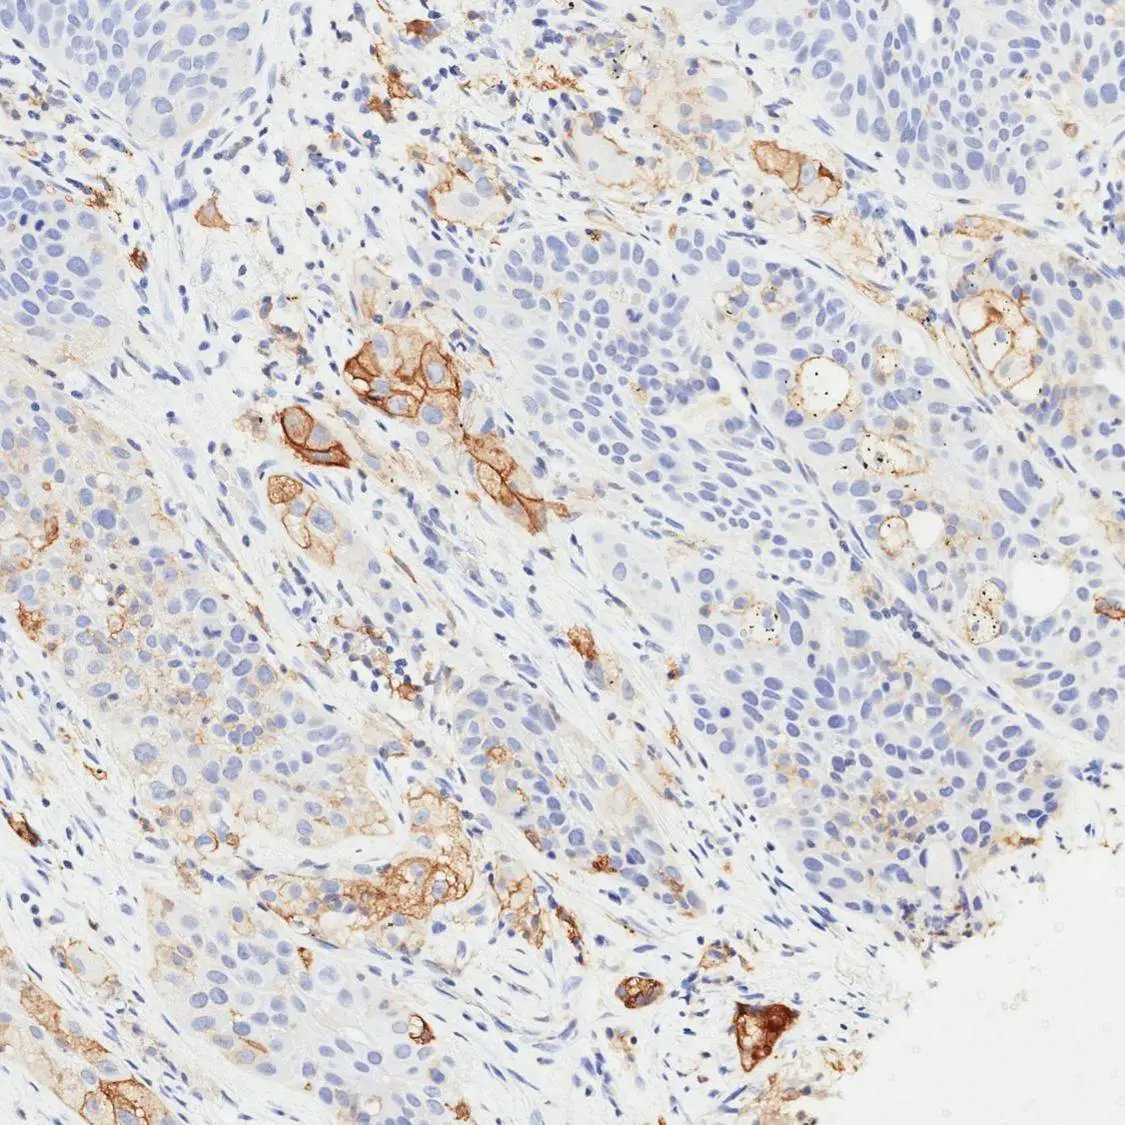

IHC-P analysis of human colorectal adenocarcinoma (COAD) tissue using GTX639925 PD-L1 antibody [H302] HistoMAX™.

PD-L1 negative colorectal adenocarcinoma surrounded by numerous PD-L1 positive inflammatory cells.